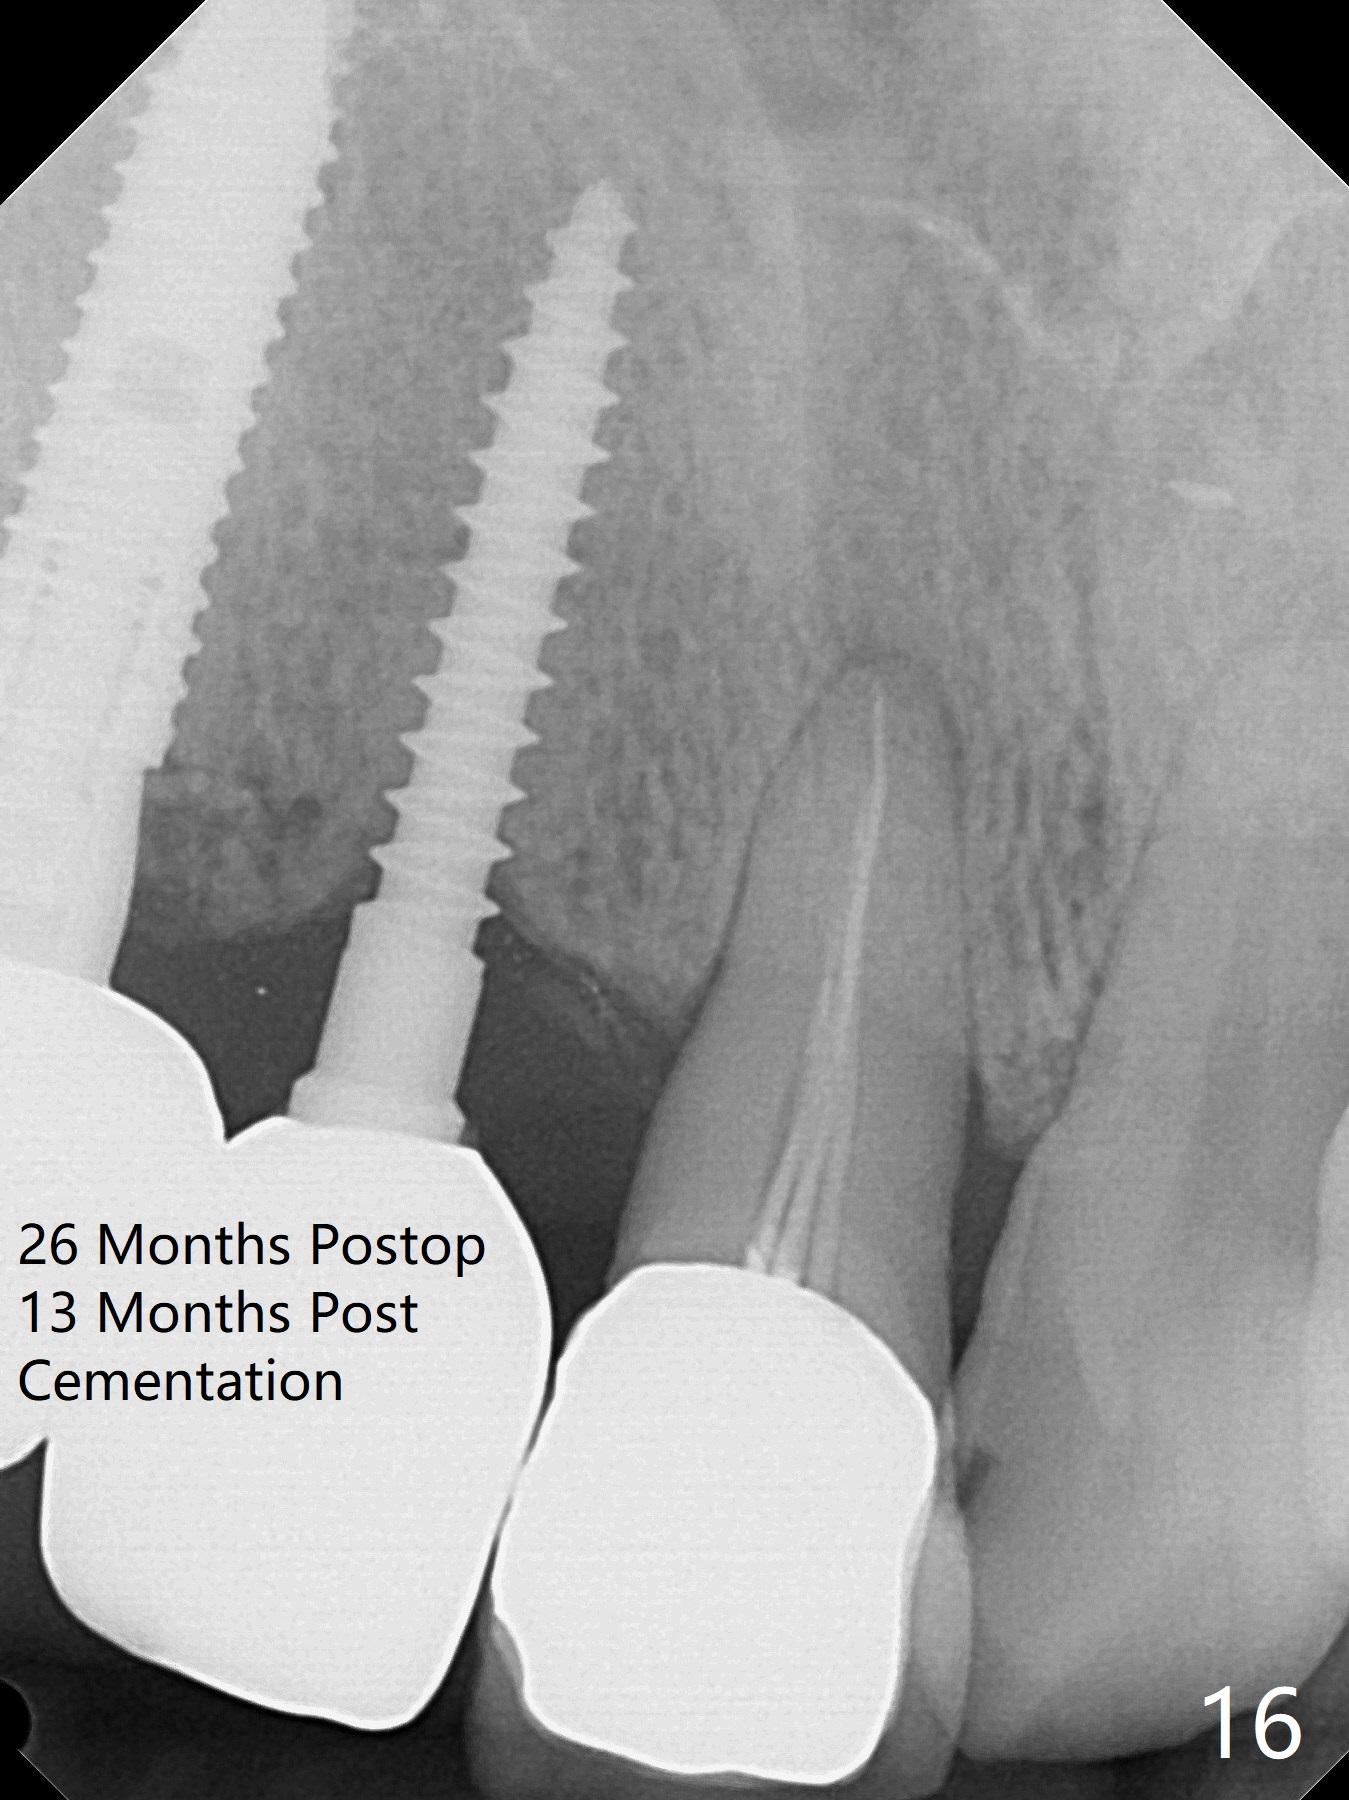

Since the ridge at #7 is ~ 4 mm, a 2.5x14 mm 1-piece implant is placed (Fig.8) after 1.2 mm (Fig.7), and 1.5 mm drills at 12 mm and 2 mm drill at 8 mm. Later the implant is placed deeper (Fig.10). There is no bone loss 7 or 12 months postop, respectively (Fig.11,12). After Diode gingivectomy, there is papillary formation (Fig.13). No provisional is provided after impression (with the abutment torqued at #6) for oral hygiene. With access holes at #6 and 7, crowns are bonded with minimal residual cement (Fig.14 <, which is removed later). There is no hard (Fig.15,16) or soft (Fig.17 *) atrophy 26 months postop, i.e., 13 months post cementation, due to the presence of socket shield (Fig.15 <, as compared to Fig.1). In fact the tooth #8 has mobility and fremitus (short root/poor crown/root ratio, Fig.16); occlusal adjustment is done 13 months post cementation. The crown is dislodged 2 years 1 month post cementation; a prefabricated post is being tried in (Fig.18). There is no atrophy, bone loss or infection at #6 (with socket sheath (*)) or 7 two years 5 months post cementation (Fig.20-27).